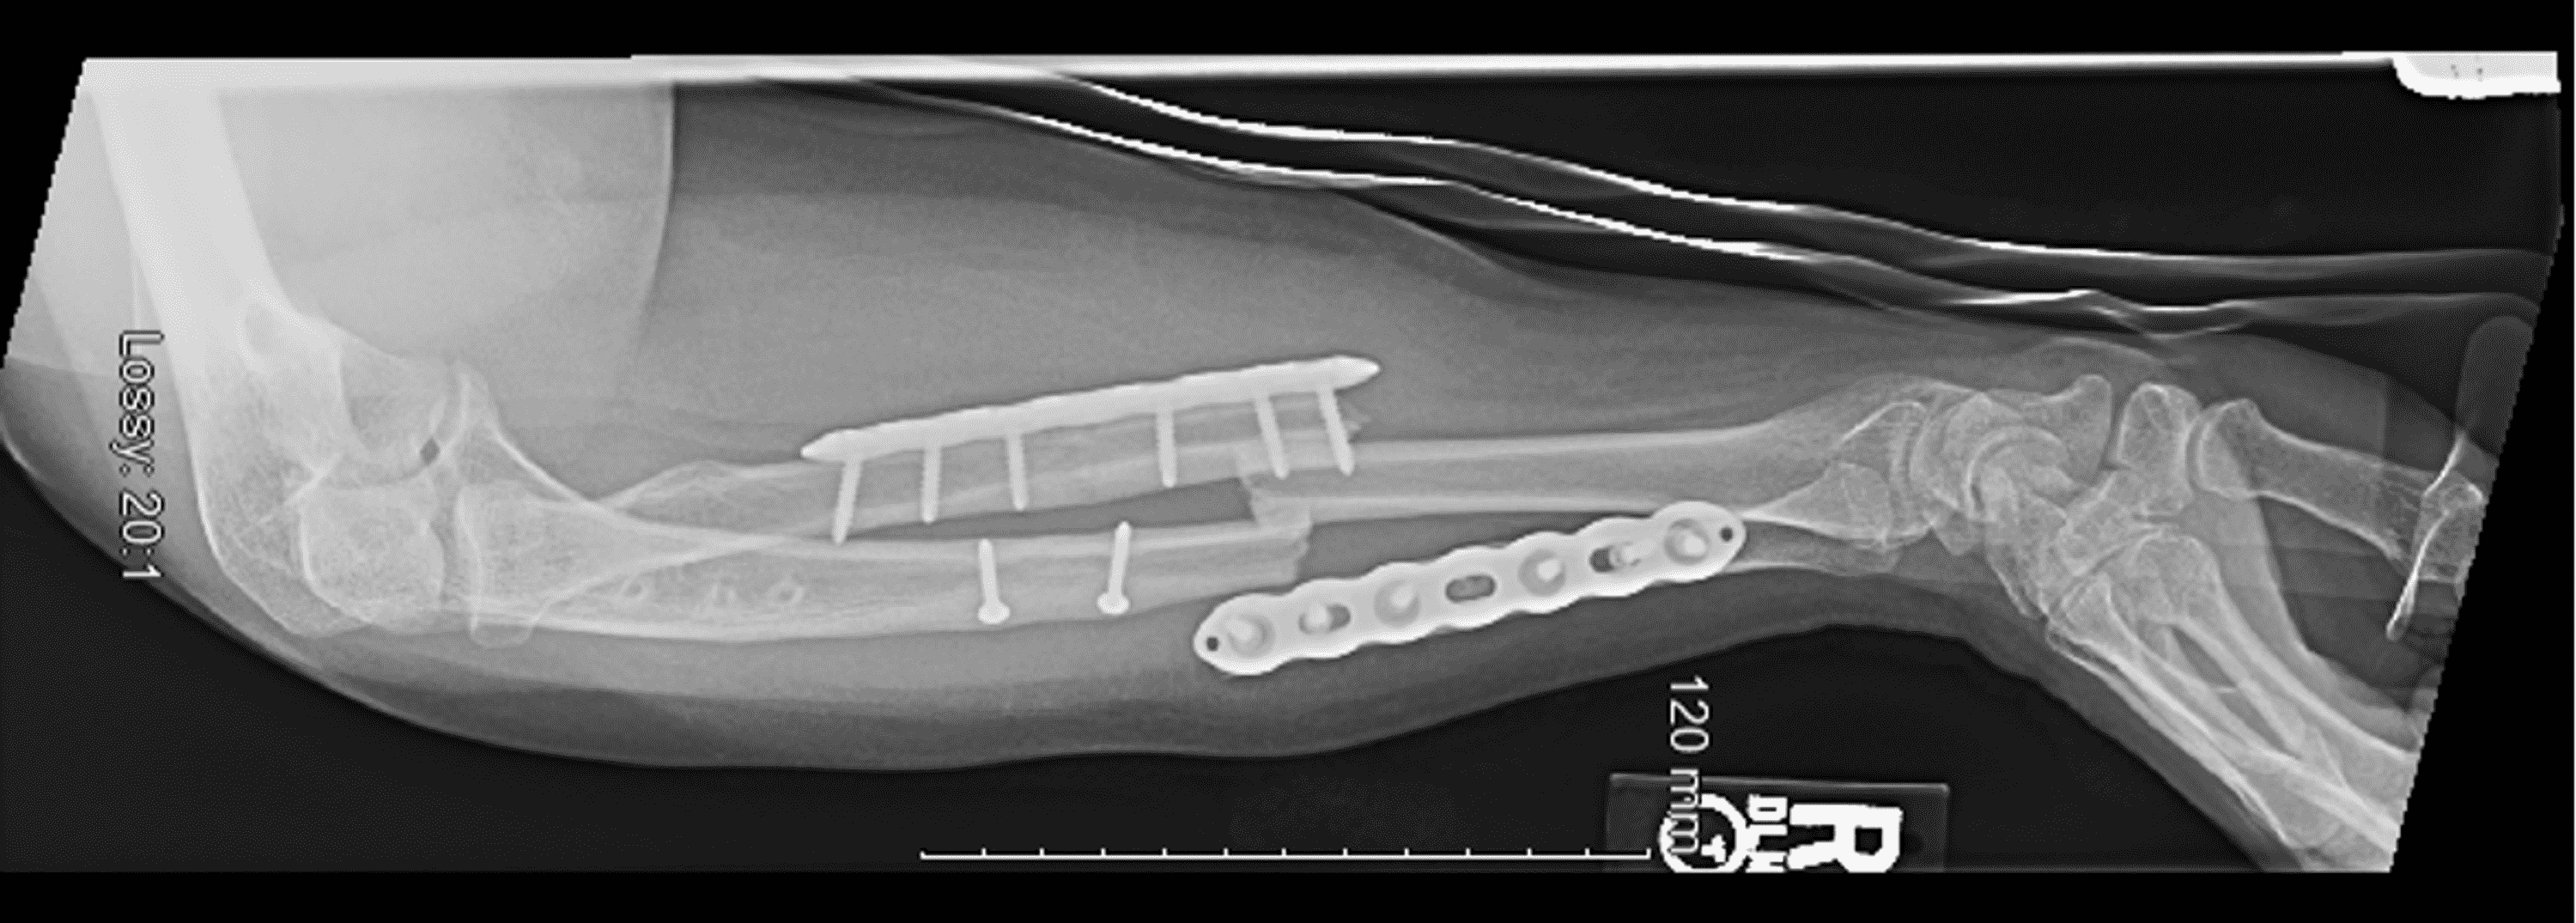

Cureus Intramedullary Nail and Plate Combination Technique for Peri Forearm Anatomy Radiograph — frontal and side views of the forearm show the radiological bony structures of the radius and ulna. See some great forearm fracture cases. these radiographs depict the basic bony anatomy of the forearm. Image source from wikiradiography (wetpaint) here. The forearm contains two bones that lie parallel to each other—the radius and ulna. — radiographic anatomy. Forearm Anatomy Radiograph.

Cureus Intramedullary Nail and Plate Combination Technique for Peri Forearm Anatomy Radiograph — radiographic anatomy of the forearm. The forearm contains two bones that lie parallel to each other—the radius and ulna. these radiographs depict the basic bony anatomy of the forearm. See some great forearm fracture cases. — frontal and side views of the forearm show the radiological bony structures of the radius and ulna. Image source from. Forearm Anatomy Radiograph.

Cureus Intramedullary Nail and Plate Combination Technique for Peri Forearm Anatomy Radiograph Image source from wikiradiography (wetpaint) here. See some great forearm fracture cases. — frontal and side views of the forearm show the radiological bony structures of the radius and ulna. these radiographs depict the basic bony anatomy of the forearm. The forearm contains two bones that lie parallel to each other—the radius and ulna. — radiographic anatomy. Forearm Anatomy Radiograph.